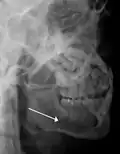

lateral oblique image demonstrating a fractured mandible.

-

Towne's view of a bilateral condyle fracture. White arrow is a fracture on the neck of the condyle. Black arrow shows the condyle pulled to the medial. The same injury can be seen on the opposite side -